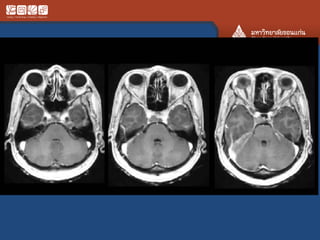

#Germinoma

• 5-25 yrs

• AKA dysgeminoma, intracranail seminoma

• MC at stalk and hypothalamus and pineal

region

• Crawls along floor of the 3rd vent

• Ddx: LCH, craniopharyngioma

• Adult: sarcoid, lymphoma